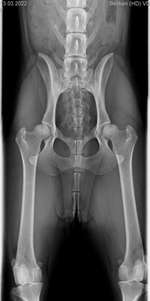

Unsere Hündin, die wir jetzt 4 Monate haben, musste zur Blutabnahme. Verdacht auf Leishmaniose. Sie kommt aus Kroatien und es geht ihr seit einer Woche nicht gut.